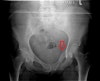

X-ray : 골반 골절(Pelvic fracture)

* 수직 불안정성을 의미하는 방사선학적 소견 : 수술적 치료 필요

제5요추 횡돌기 골절

두부방향으로 전위 > 1cm

천골 외측부 또는 좌골극 견열 골절

치골결합 이개 > 2.5cm

전위된 천골 골절

Push-pull test 상 1cm 이상의 두부 방향으로의 전위